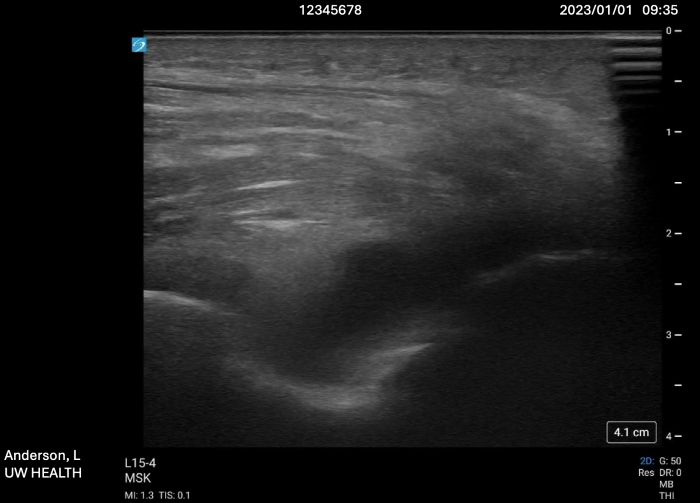

It is also imperative to remove all identifiers from the ultrasound image themselves, beyond the medical record number. For example, the date and time of the POCUS study and information about the performing user and the institution where the ultrasound was performed should be removed. Further, did you know that when using the ‘crop’ feature in PowerPoint or Keynote, the original ultrasound clips with the patient information can still be retrieved? Hidden data within the ultrasound image files themselves lives ‘metadata’, which can also be tracked back to the patient. There are numerous editing softwares available; we recommend first running all of your ultrasound clips through the ‘ClipDeidentifier’ tool available on the Core Ultrasound website. This tool allows you to crop multiple clips from the same series at once and removes the hidden ‘metadata’ from the images themselves. The generated cropped images from ClipDeidentifier are generally safe to distribute without exposing the patient’s PHI. Remember– protecting the patient's information is ultimately your responsibility!

Case #2: “A 92-year-old male with a history of alcohol use, gout (last episode in May 2021), hypertension well-controlled with hydrochlorothiazide, presented to the University of Wisconsin ED with right elbow pain and swelling. Ultrasound is shown below:”

Try instead: “An elderly male with a history of alcohol use, gout, and well-controlled hypertension, presented to the emergency department with elbow pain and swelling. Ultrasound is shown below:”